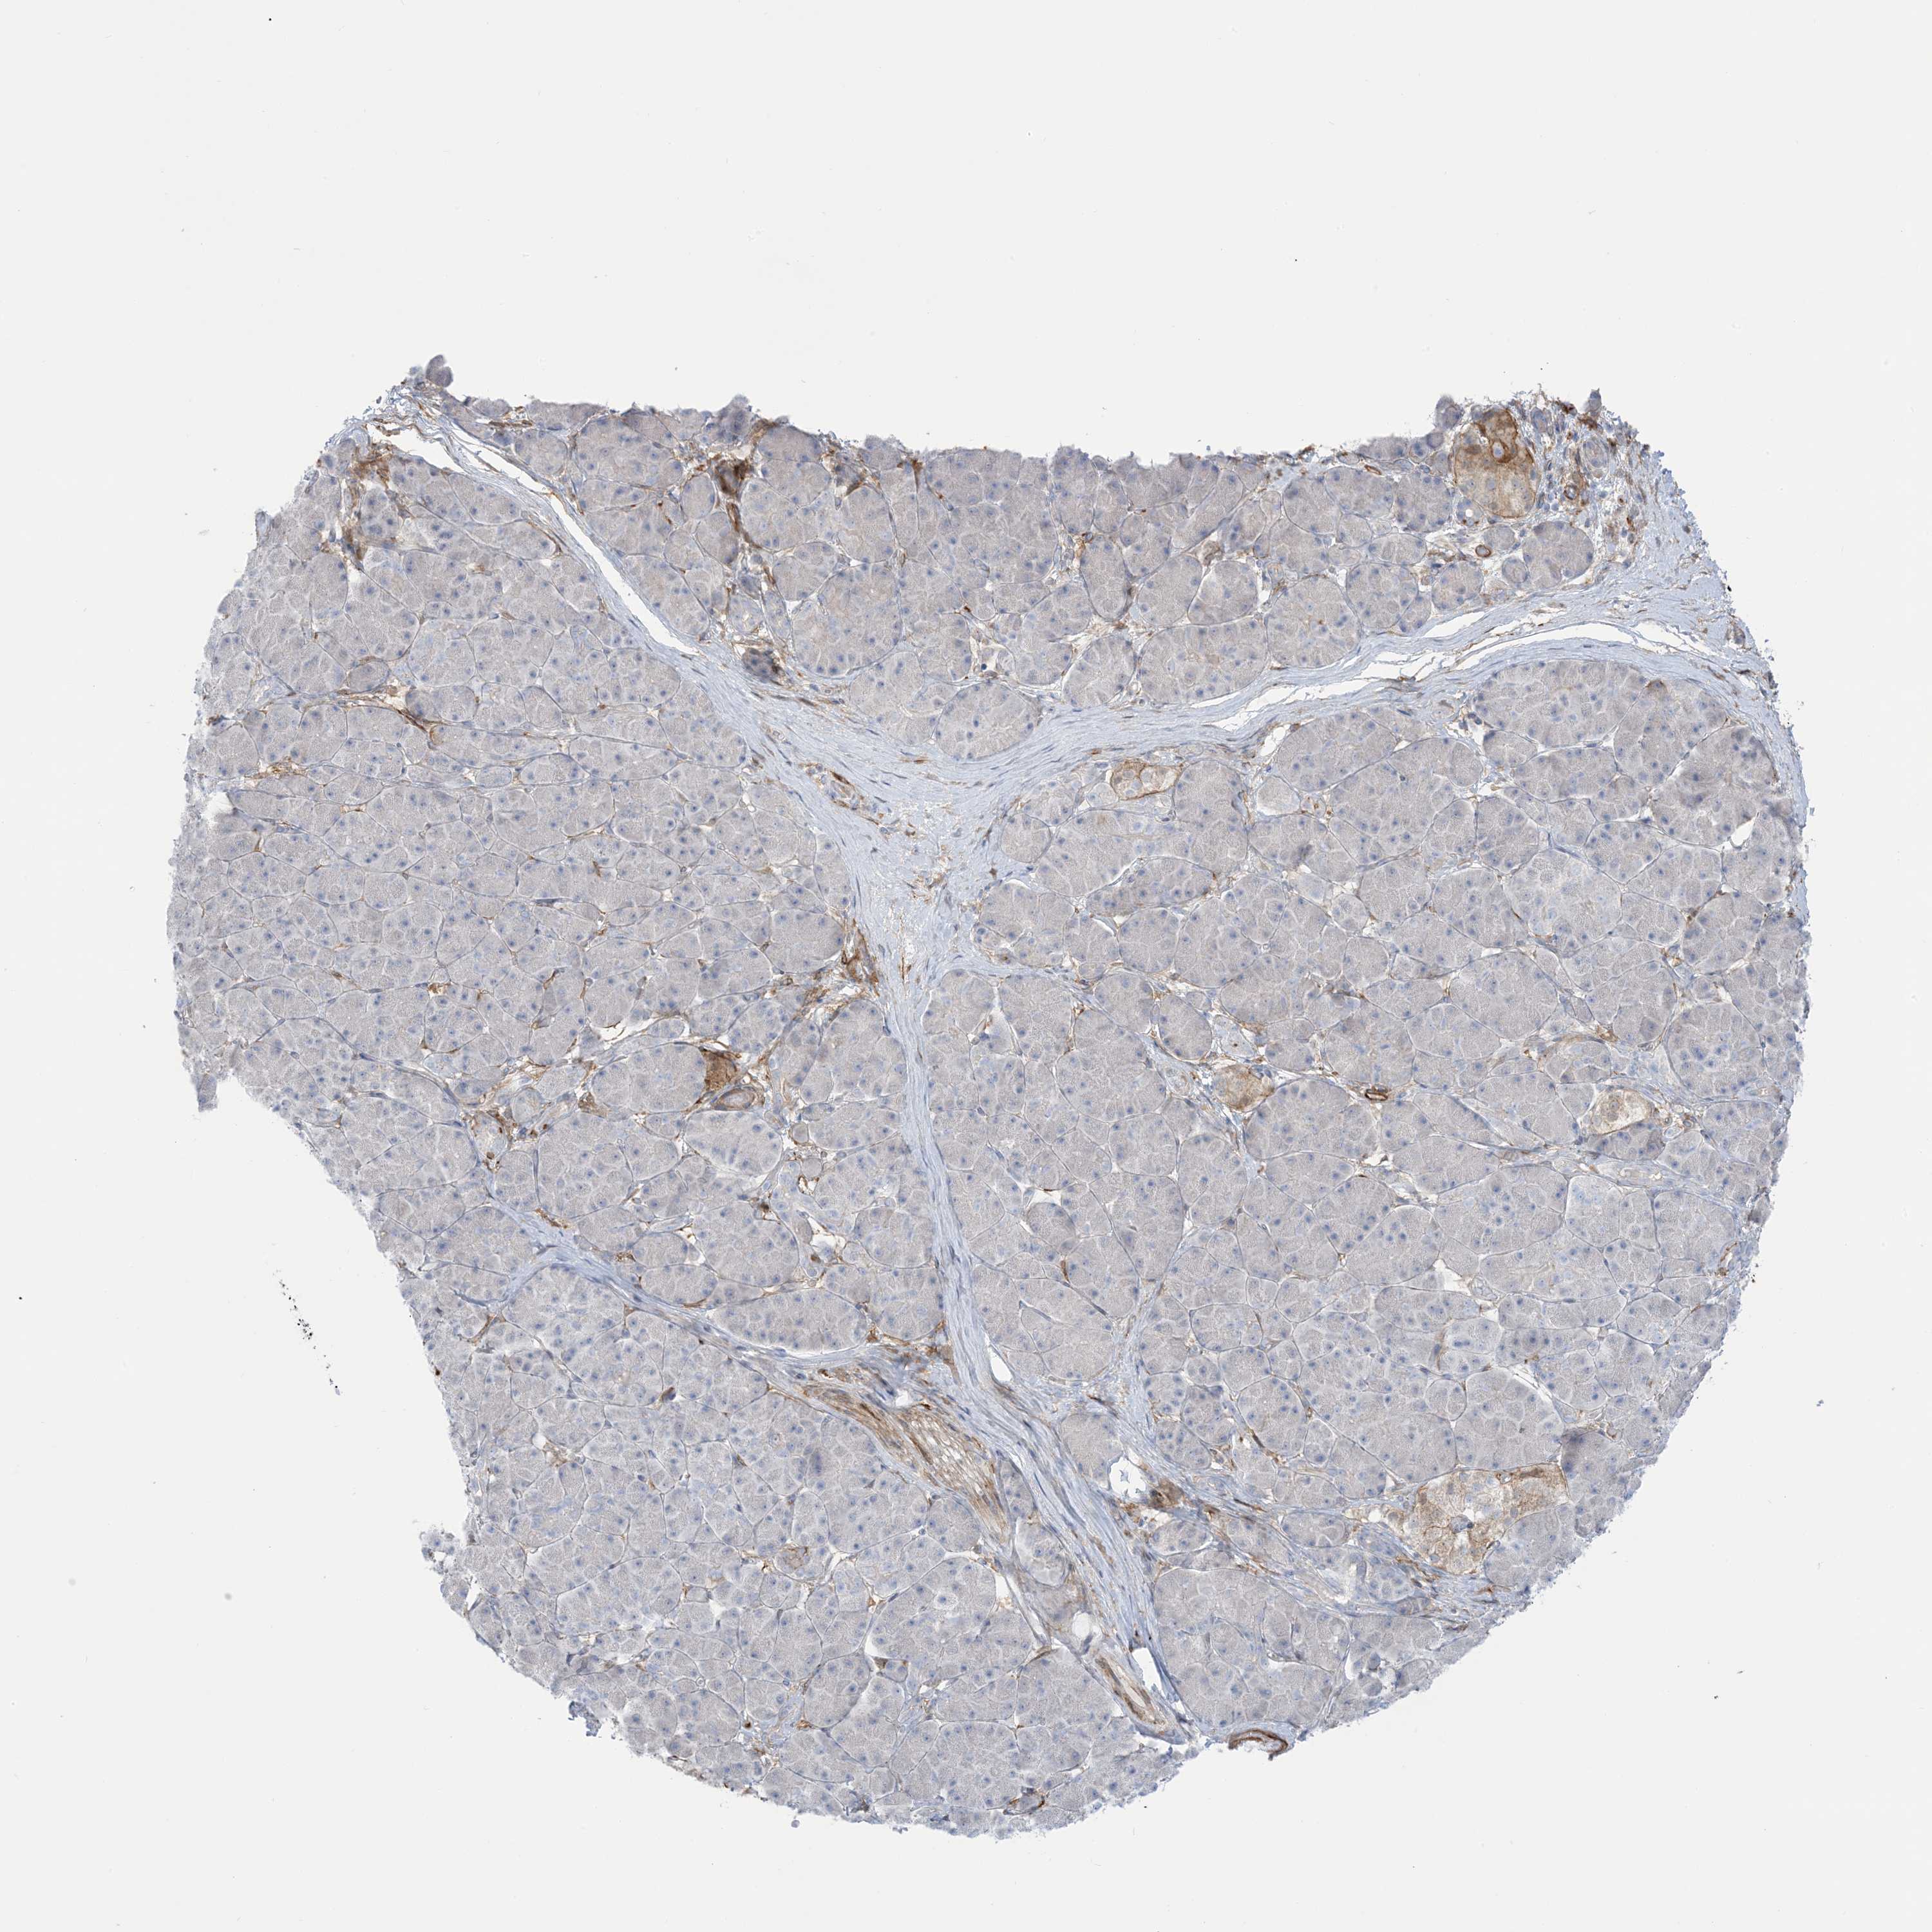

PANCREATIC CANCER - Protein expressioni

A mouse-over function shows sample information and annotation data. Click on an image to view it in a full screen mode. Samples can be filtered based on level of antibody staining by selecting one or several of the following categories: high, medium, low and not detected. The assay and annotation is described here.

Note that samples used for immunohistochemistry by the Human Protein Atlas do not correspond to samples in the TCGA dataset.

Antibody stainingi

Antibody staining in the annotated cell types in the current human tissue is reported as not detected, low, medium, or high, based on conventional immunohistochemistry profiling in selected tissues. This score is based on the combination of the staining intensity and fraction of stained cells.

Each image is clickable and will lead to virtual microscopy that enables deeper exploration of all samples and also displays staining intensity scores, fraction scores and subcellular localization as well as patient and tissue information for each sample.

Antibody HPA032024

Antibody HPA032025

Staining

High

Medium

Low

Not detected

Intensity

Strong

Moderate

Weak

Negative

Quantity

>75%

75%-25%

<25%

None

Location

Nuclear

Cytoplasmic/membranous

Cytoplasmic/membranous,nuclear

Adenocarcinoma, NOS